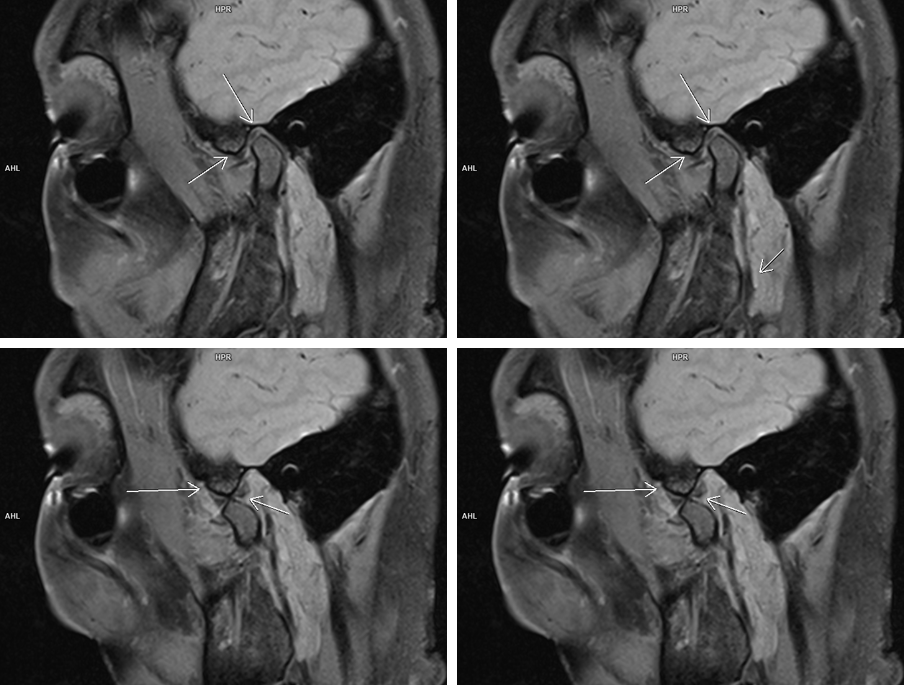

Figura 2: achiziţie oblic sagital PD cu saturaţia grăsimii în planul articulațiilor temporo-mandibulare cu gura închisă (rând superior) și cu gura deschisă (rând inferior); pentru evidențierea unei mișcări normale a discului articular

Pe imaginile și secvențele cine prezentate se evidențiază modificare de formă a condilului mandibular stâng ce şi-a pierdut sfericitatea şi asociază prezenţa de modificări de tip edematos-inflamator în osul subcondral – modificare apărută probabil datorită unei asimetrii dentare astfel încât apare incongruența suprafețelor articulare iar pacientul prezintă cracmente articulare și blocare periodică a articulației; în principiu, asimetriile dentare (mușcături incorecte) duc în timp la probleme ale articulației, din cauza faptului că articulația este foarte mult solicitată.